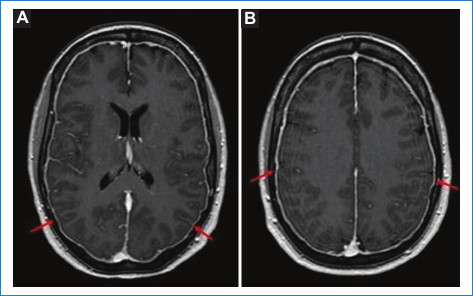

RM: es el método de elección y su sensibilidad es superior a la de la TC.

Signos directos: en los senos venosos se evidencian defectos de flujo que se traducen en alteración de la señal (Fig. 4). La intensidad de señal del trombo es similar a la evolución de la sangre en un hematoma18:

Trombo agudo (1-5 días): la desoxihemoglobina es la molécula dominante. El coágulo es isointenso en T1, hipointenso en T2 y marcadamente hipointenso en GRE (esto puede simular un vacío de flujo)18,19.

Trombo subagudo temprano (entre los días 6 y 15): se produce la oxidación de la molécula de desoxihemoglobina a metahemoglobina. El coágulo es hiperintenso en las secuencias T1 y T218,19.

Trombo subagudo tardío (> 15 días): continúa la desintegración de la molécula de hemoglobina. Esta etapa puede ser un reto, ya que la trombosis crónica muestra una recanalización parcial y la señal del coágulo es iso-hiperintensa en T2 e isointensa en T12,18.

Trombo crónico (> 30 días): el trombo es isointenso o hiperintenso en T2 e hipointenso en T1. Se ha observado que, luego del contraste, a veces, el seno presenta un realce similar al del seno normal, probablemente vinculado a la organización del trombo con signos de vascularización intrínseca18,19,20.

Signos indirectos: los hallazgos en la RM son los mismos que en la TC, aunque más sensibles y específicos. Comprenden el infarto venoso que coexiste con edema cerebral vasogénico o citotóxico con o sin hemorragia intraparenquimatosa (Fig. 5) 18,19,20.